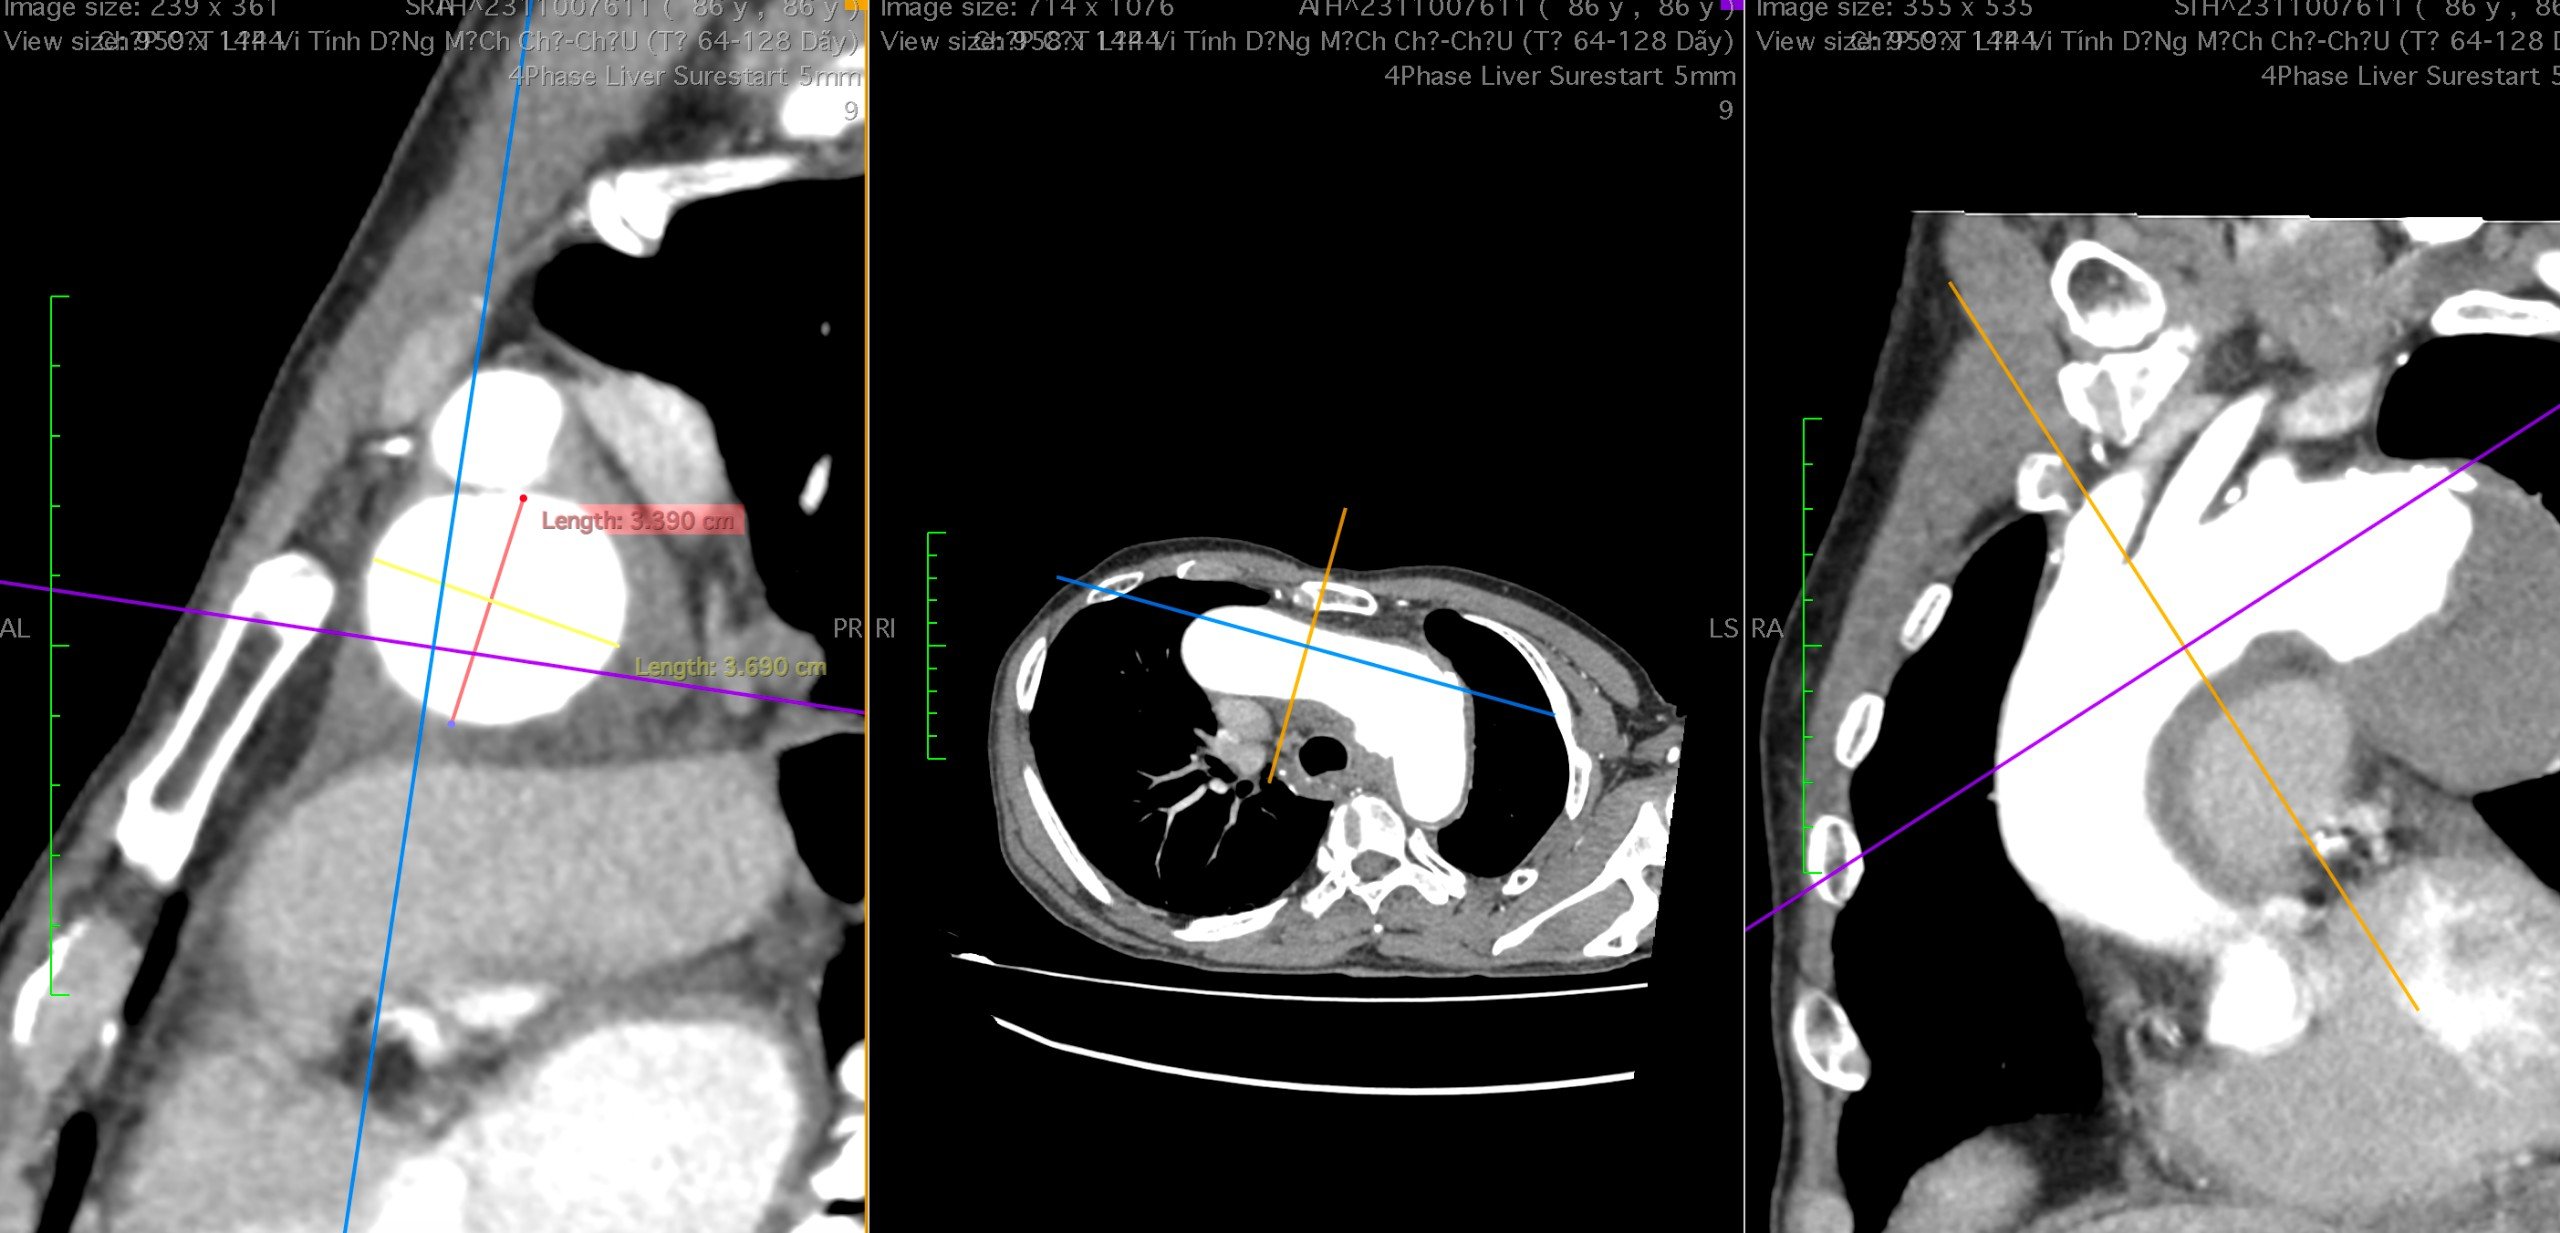

Sau khi thăm khám, làm các xét nghiệm cận lâm sàng và chụp MSCT, bệnh nhân được chẩn đoán phình lớn động mạch chủ ngực ngay dưới động mạch dưới đòn trái, kích thước 57 x 59mm, khối phình gây triệu chứng đau ngực và khàn tiếng do liệt dây thần kinh quặt ngược trái.

Hình ảnh khối phình lớn trên phim chụp CLVT